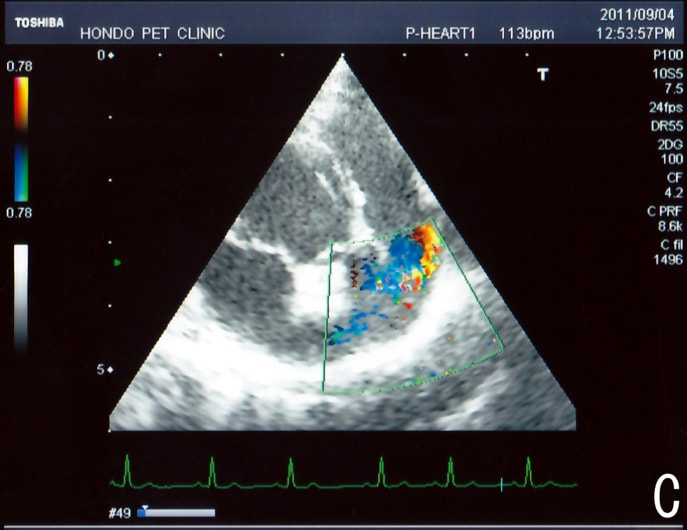

C:超音波 僧帽弁逆流、三尖弁逆流、大動脈弁逆流の動画

胸部レントゲン検査において重度の心拡大と肺水腫が認められた。超音波検査では、重度の僧帽弁閉鎖不全症、三尖弁閉鎖不全症、中程度の大動脈弁閉鎖不全症を合併していることが判明した。三尖弁逆流速度から肺高血圧症が示唆された。